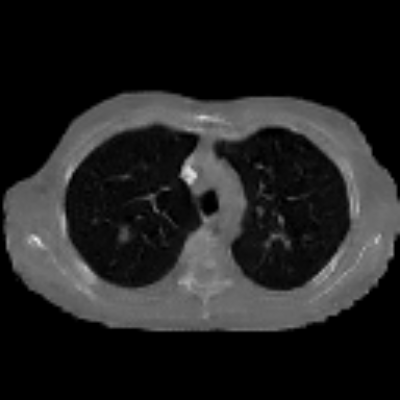

| Axial | Coronal | Sagittal | |

| X2CTGAN | ![]() |

![]() |

|

| DX2CT | ![]() |

| Ground-truth | ![]() |

Figure 3 and Table I(a) using biplanar X-rays show that proposed DX2CT can outperform three existing SOTA methods. Figure 3 shows that DX2CT can provide more accurate overall shapes and details compared to the existing methods. The quality of reconstructed CT slices in the axial plane is less satisfactory than those in the other planes. The reason is that the axial plane is perpendicular to the planes of biplanar X-rays so there exists less spatial (i.e., depth) information in the axial plane. Without using the perceptual loss [33], proposed DX2CT gave comparable LPIPS results with PerX2CTs using [33] in training. Compare their LPIPS results in Table I(a).